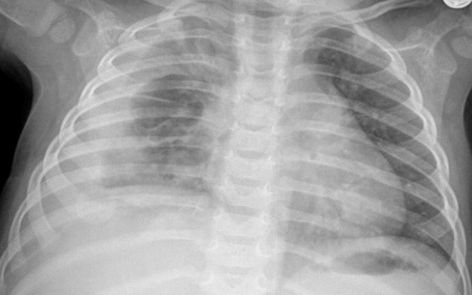

Varón de dos años con derrame pleural.

Derrame pleural

Apreciaremos un aumento de la densidad del hemitórax afecto, con borramiento del seno costofrénico y pérdida de la definición del hemidiafragma correspondiente. Puede existir desplazamiento mediastínico dependiendo de la magnitud del derrame.